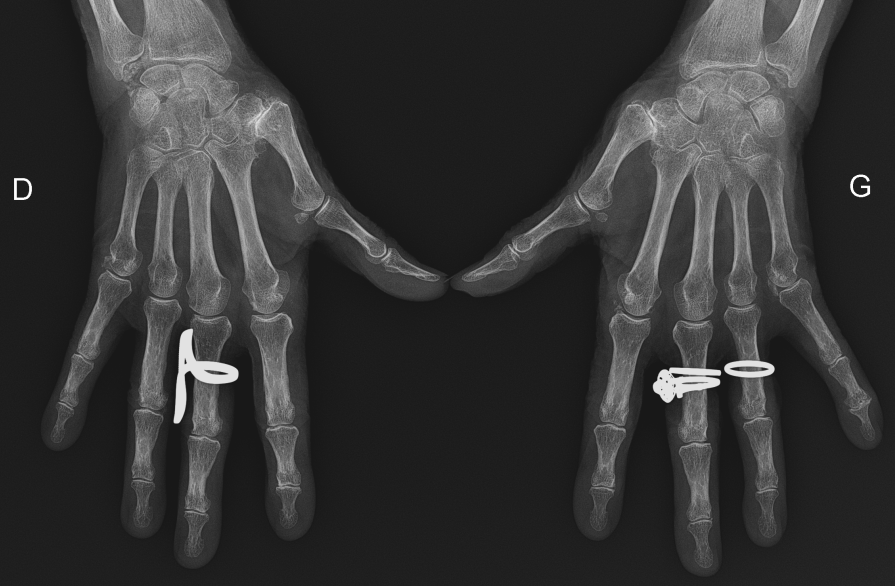

Une patiente de 77 ans présente depuis 48 heures une tuméfaction douloureuse de la main gauche, d’apparition rapide, avec impotence fonctionnelle partielle. La main est chaude, oedématiée, sans notion de traumatisme récent. Vous évoquez une arthrite aiguë microcristalline.

Il s’agit d’une mono- ou oligoarthrite aiguë de la main chez une patiente âgée, évocatrice en premier lieu d’une arthropathie microcristalline, notamment à cristaux de pyrophosphate de calcium. Le diagnostic différentiel principal est l’arthrite septique, qui doit toujours être éliminée en cas d’articulation chaude et inflammatoire. La radiographie peut montrer des calcifications cartilagineuses en faveur d’une chondrocalcinose. La ponction articulaire, quand elle est réalisable, permet de rechercher des cristaux et d’éliminer une infection. Le traitement repose sur le repos, la glace, les AINS ou la colchicine selon le terrain, voire une corticothérapie après élimination d’une infection.